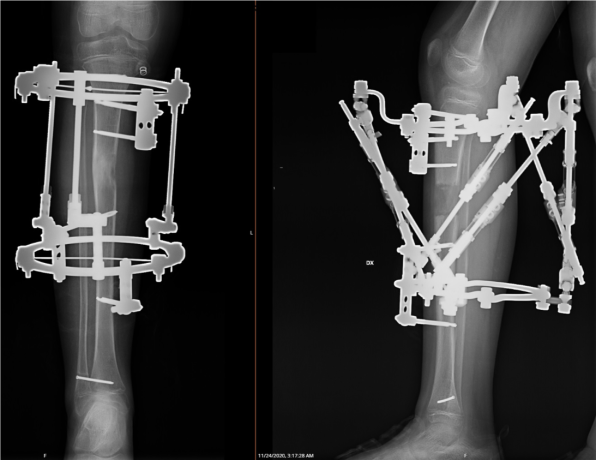

1. Ekstremitāšu rekosntruktīvā ortopēdija nozīmē operāciju un tai sekojošu operētās zonas korekciju ar ārējās fiksācijas aparāta, t.s. ortopēdiskā heksapoda palīdzību.  Operācija noris, izmantojot spinālo vai vispārējo anestēziju, un ilgst līdz 2 stundām. Pacientam klīnikā jāuzturas vienu diennakti.

2. Operācijas laikā tiek veikta osteotomija (kontrolēts lūzums) un uzstādīts ortopēdiskais heksapods – ārējās fiksācijas aparāts, ar kura palīdzību iespējams veikt gandrīz jebkuras deformācijas precīzu korekciju.

Ekstremitāšu rekonstruktīvā ortopēdija notiek ķirurģiski ar ārējās fiksācijas - t.s. ortopēdiskā heksapoda palīdzību.